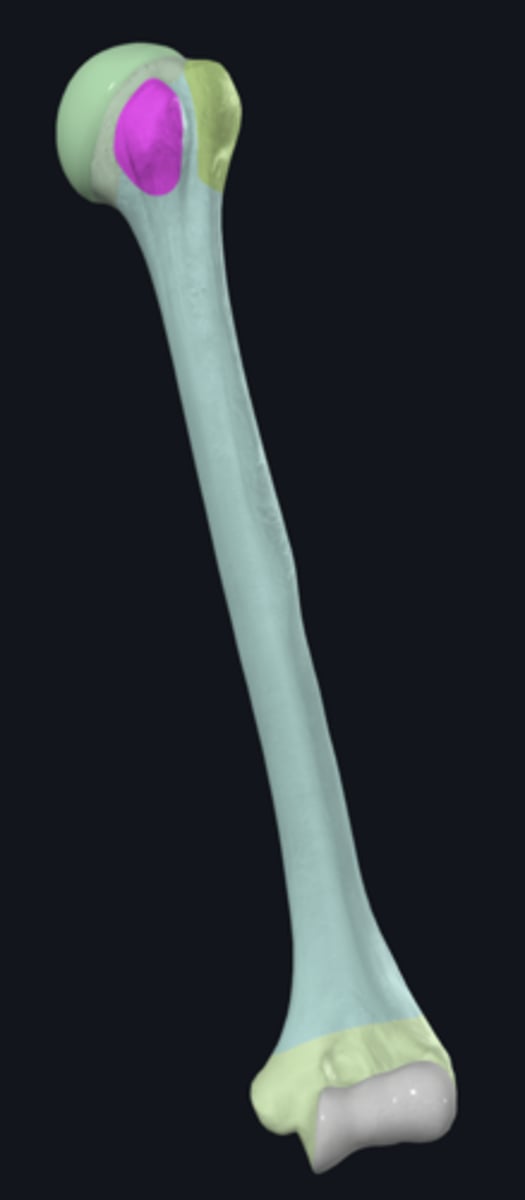

anatomical neck of humerus

body of humerus

condyle of humerus

greater tubercle

head of humerus

lesser tubercle

anterior border of humerus

anterolateral surface of humerus

anteromedial surface of humerus

lateral border of humerus

lateral epicondyle of humerus

lateral supracondylar ridge

medial border of humerus

medial epicondyle of humerus

medial supracondylar ridge

posterior surface of humerus

Capitulum

coronoid fossa

Crest of greater tubercle

crest of lesser tubercle

deltoid tuberosity

groove for ulnar nerve

bicipital groove

olecranon fossa

radial fossa

radial groove

surgical neck of humerus

trochlea